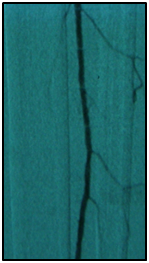

Endovascular procedure was done with antegrade access in the ipsilateral common femoral artery, diagnostic angiography confirmed: Patency of the femoral-popliteal axis, occlusion of the posterior and anterior tibial arteries, two critical stenotic lesions in the fibular artery and revascularization of the dorsalis pedis and plantar arteries by the fibular artery. To treat the fibular critical atherosclerotic lesions were performed a percutaneous transluminal angioplasty using a 0.0018in.guidewire, catheter support and a catheter balloon (3,0x6 mm and 3,5x 15mm).

Final angiographic control showed patency of the fibular artery and dorsalis pedis, with direct flow for the first metatarsal artery, thus guaranteeing enough flow to heal the ulcer in six months after the procedure. In conclusion endovascular treatment has a high technical eligibility with good reported outcomes and represents an alternative for diabetics with CLI Disease (Figure 1 and 2).

• Figure 2 From left to right showing percutaneous transluminal BTK balloon angioplasty, and revascularization of the dorsalis pedis and plantar arteries by the fibular artery.